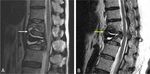

Figure 3.  Preoperative MRI predictors of the cement bridging phenomenon include (A) fluid accumulation

(white arrow) and (B) hypointense signaling (yellow arrow), indicating a redundant anterior longitudinal

ligament, around the space anterior to the abutting vertebral bodies and the corresponding intervertebral disc.

lateral-view plain film (odds ratio [OR] = 4.46, p = 0.014), fluid accumulation (OR = 36.27, p < 0.001) or hypoin-

tense signaling (OR = 15.67, p < 0.001) around the space anterior to the abutting vertebral bodies and the cor-

responding intervertebral disc on MRI (Fig. 3). Furthermore, 14 vertebrae (70%) that were previously cement-

augmented vertebrae demonstrated increased cement volume due to the cement bridging phenomenon. No

statistical significance in patient age, sex ratio, BMI, T-score of BMD or injected cement volume was found

between the bridging and nonbridging groups (p > 0.05).